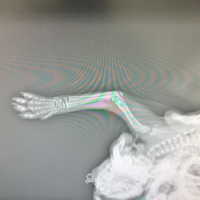

Kırık olunca belirgin olabiliyor burda doku bütünlüğü bozulmuş oluyor kırıklarda

Röntgende görünmüyor tabi hekim anlar birbirinden ayrılmış görünmüyor yapay zekadan da tehit etmek için bilgi aldım

Bu röntgende doku bütünlüğü bozulmuş görünmüyor yani kırık görünmüyor